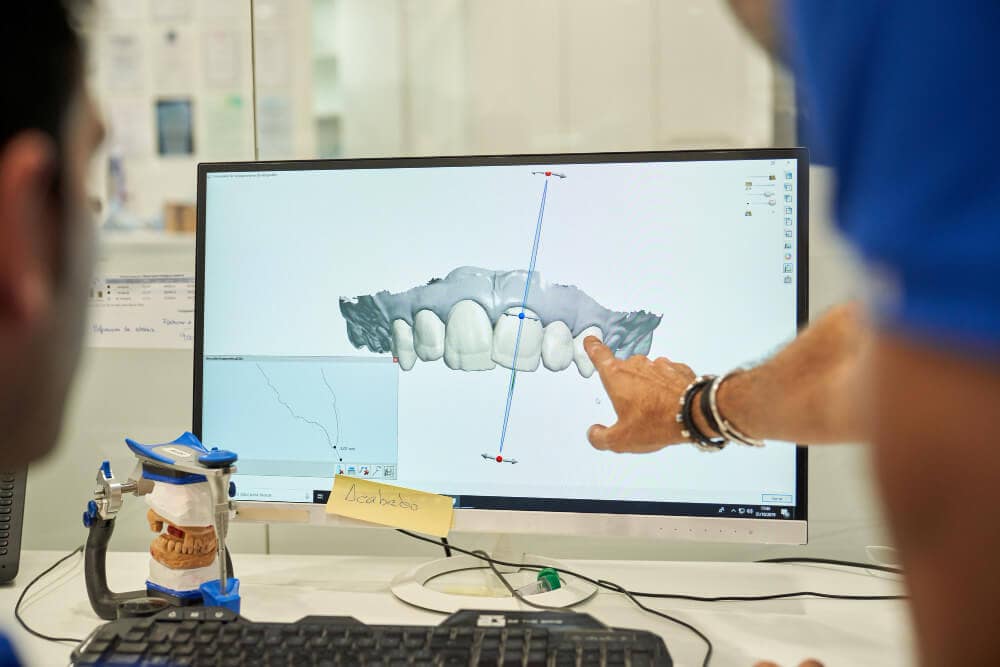

Lo último en tecnología

Tecnología de primer nivel para todos los procesos de nuestros tratamientos odontológicos.

Tecnología de primer nivel para todos los procesos de nuestros tratamientos odontológicos.